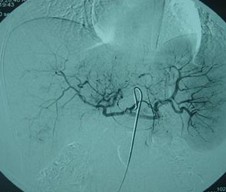

患者情況:肝細(xì)胞性肝癌,術(shù)后復(fù)發(fā),右肝內(nèi)多個(gè)病灶。治療方案:瘤內(nèi)注射今又生1×1012VP/次/周,共8周,同時(shí)聯(lián)合肝動(dòng)脈化療栓塞(TACE),1次/月,共2次。下圖示:左側(cè)上下兩圖為治療前,CT示血管豐富;右側(cè)上下兩圖為治療一個(gè)療程后,碘油均勻沉積,腫瘤血供減少。

治療前

治療后